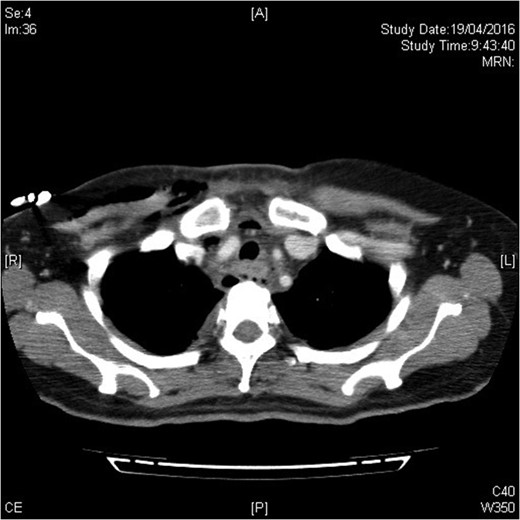

The urgent contrast computed tomography neck and thorax revealed multiple gas locules in bilateral deep cervical spaces, loculated right pleural effusion and right chest wall subcutaneous emphysema. The overall radiological features were suggestive of underlying deep neck space infection by gas-forming organisms complicated with descending mediastinitis and empyema thoracis (see Figs 1–3).

Infection extending down to superior mediastinum and chest wall.